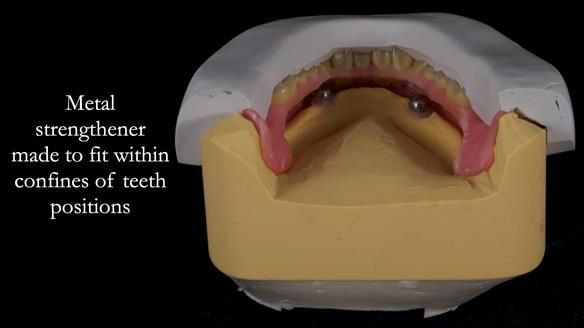

2. The upper denture, horseshoe-shaped and metal-reinforced, rocks on the ridge, causing wear on Locator abutments and a fractured upper right tooth.

The detailed clinical situation and treatment process are outlined below, with clinical work provided by me and technical work by Rowan Garstang. New complete implant supported complete dentures were made. The new upper denture had ‘almost’ full palatal extension for the non-splinted implants following ITI guidelines. A decision was reached to retain the worn Kerator attachments, as their removal could potentially accelerate implant failure. The treatment spanned five visits for denture fitting and one review. Alisdair expressed great satisfaction with the treatment, noting a significant enhancement in his overall quality of life.